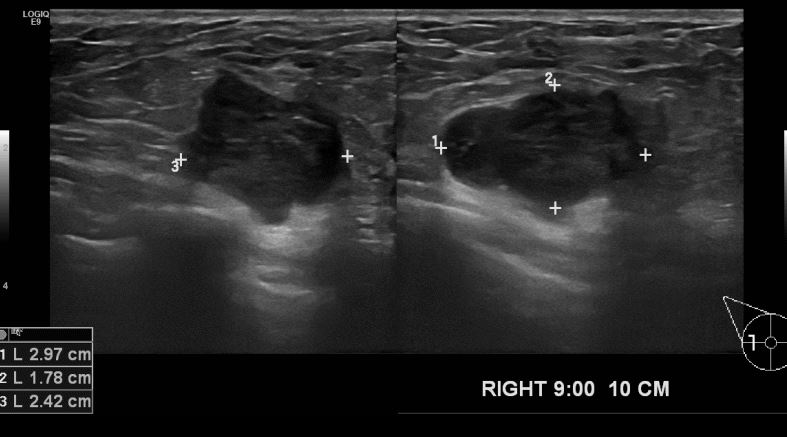

상기환자  3개월전에 우연히  우측유방멍울 발견하여 내원하신 30대 수유맘으로

초음파진행후 우측방향 9시방향으로 의심스런 멍울있어 중심핵생검실시한후

침윤성유관암 진단되셨습니다.